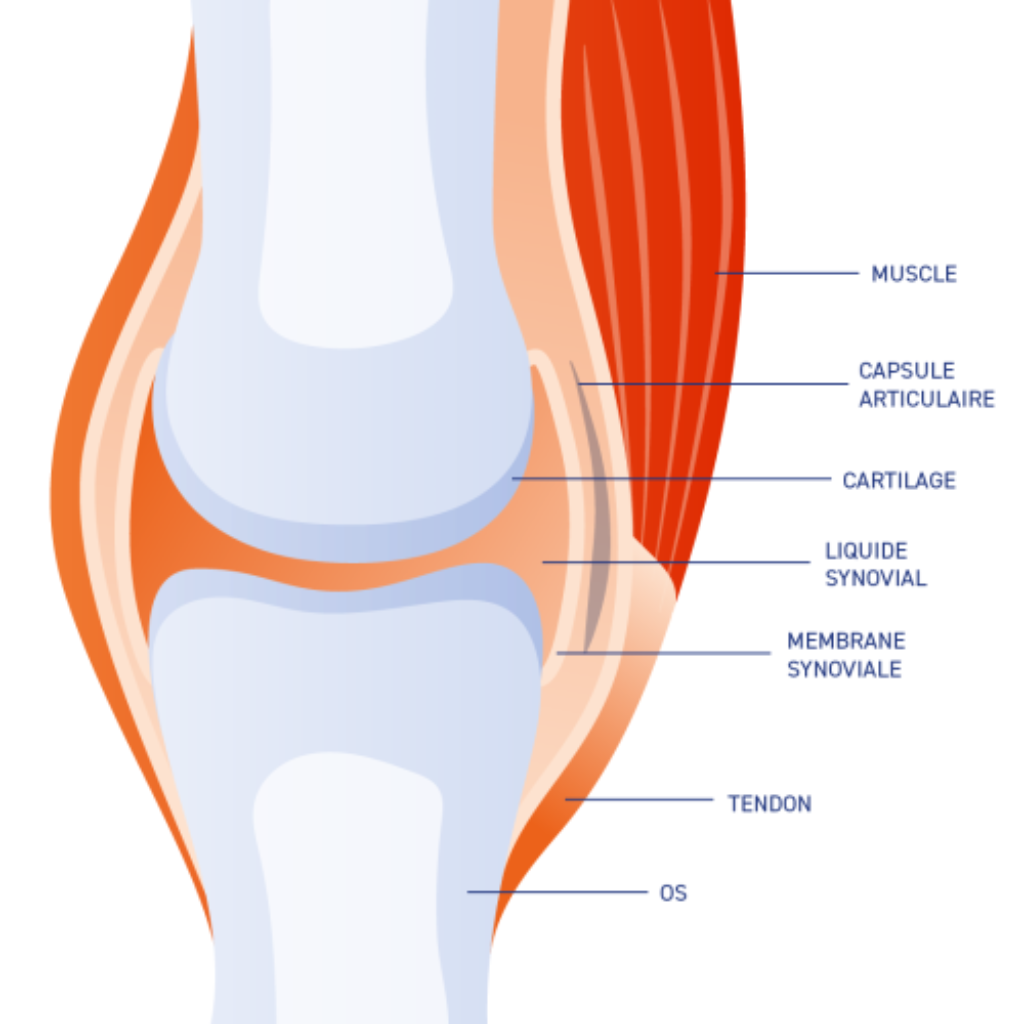

Pour bien appréhender les moyens de protéger les articulations de votre chat, il est important de saisir en détail leur structure et leur fonction.

L’articulation est une structure complexe, située à la jonction de deux os. Elle permet les mouvements en douceur tout en maintenant la stabilité du squelette.

Ses composants principaux :

Le cartilage articulaire

Il s’agit d’un tissu conjonctif dense, lisse et élastique, qui recouvre les extrémités des os au niveau des articulations. Son rôle est double : d’une part, il agit comme un amortisseur en absorbant les chocs mécaniques, et d’autre part, il réduit la friction entre les os pendant le mouvement. Sans cartilage, les os se frotteraient directement les uns contre les autres, causant douleur et inflammation.

La capsule articulaire et le liquide synovial

La capsule articulaire est une membrane fibreuse qui entoure l’articulation. À l’intérieur, cette capsule est tapissée par la membrane synoviale, qui sécrète le liquide synovial. Ce liquide épais et visqueux lubrifie l’articulation, facilitant les mouvements et nourrissant le cartilage. En plus de lubrifier, le liquide synovial agit également comme un moyen de transport pour les nutriments essentiels aux cellules du cartilage.

Les ligaments

Ce sont des bandes résistantes de tissu conjonctif qui relient les os entre eux au niveau des articulations. Ils stabilisent l’articulation en limitant les mouvements excessifs, qui pourraient sinon entraîner des blessures.

Les muscles et les tendons

Les muscles entourant les articulations sont essentiels pour le mouvement. Lorsqu’un muscle se contracte, il tire sur le tendon, qui est une bande de tissu conjonctif solide reliant le muscle à l’os. Ce mouvement permet de plier ou d’étendre l’articulation.